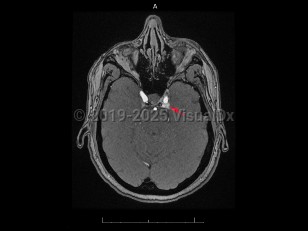

Carotid-cavernous fistula

Acquired vascular abnormality involving communication between the cavernous sinus and the carotid artery or branches. It may arise spontaneously or through injury by blunt head trauma, surgery, or vascular and connective tissue disorders, or following cavernous carotid aneurysm rupture. Onset may be delayed. Carotid-cavernous fistula (CCF) are classified as high-flow (direct) or low-flow (indirect), depending on the pressure and direction of the communicating arterial blood flow. Common symptoms include bruit, proptosis, diplopia, blurred vision, visual loss, conjunctival injection, eye pain, headache, and chemosis. CCF affects men and women about equally. Rarely, they appear bilaterally.